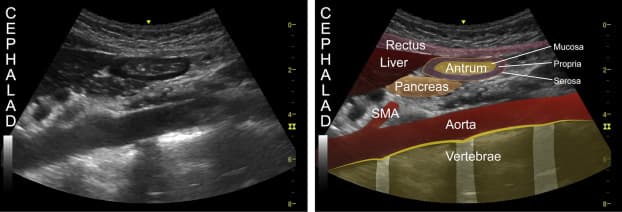

Figure 9: Ultrasound image of the abdomen showing the liver, pancreas, rectus, antrum, aorta, and more (BJA Education, 2019).

By analyzing the time it takes for the ultrasound waves to travel back to the transducer and the changes in their frequency, a computer system can create real-time images or sonograms of the internal structures, as seen in Figure 9. These images provide valuable information about the size, shape, and condition of organs, as well as the presence of any abnormalities or diseases.